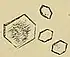

Calcium oxalate crystals can come in two varieties. Calcium oxalate monohydrate can appear as 'dumbbells' or as long ovals that resemble the individual posts in a picket fence. Calcium oxalate dihydrate have a tetragonal “envelope” appearance.[74]

Uric acid stones appear as pleomorphic crystals, usually diamond-shaped. They may also look like squares or rods which are polarizable.[74]